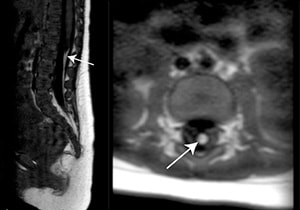

腰仙部皮膚のくぼみの精査MRIで発見された終糸脂肪腫

潜在性二分脊椎症は皮膚で覆われていますが、背部から腰仙部でのくぼみや血管腫などの皮膚異常がサインになることが知られています(15〜20%の有病率)。

当院ではエコーやMRIにてこれらの病変を検査、評価、手術適応の判断を行い手術加療を行うことが可能です。